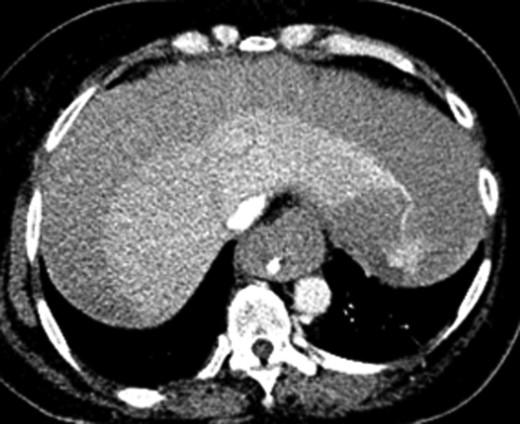

Once stable, imaging confirmed PE (Fig. 2) with a RV to left ventricle (LV) ratio of 2.1 (Fig. 3). The patient was then admitted to the ICU requiring inotropic support. Approximately 4 h later, the patient had concerning features of abdominal compartmental syndrome with increase abdominal distention and bladder pressures >25 mmHg was noted. Repeat imaging showed large volume hemoperitoneum emanating from the left hepatic lobe (Fig. 4). The patient underwent a decompressive laparotomy with a non-anatomic liver resection of segments I and II and temporary abdominal closure. Due to concerns of distal limb ischemia of the arterial cannulation site, an 8-Fr reperfusion cannula was placed in the left superficial femoral artery (SFA).

CTA abdomen performed when the patient had abdominal compartmental syndrome requiring massive transfusion protocol. CTA showing extensive hemoperitoneum with active extravasation from the left lobe of the liver.